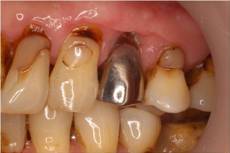

インプラント周囲炎

Perio Wave+Er:YAGレーザー+コールドレーザーの例です。

左の画像が照射前です。3ヶ月でここまで治癒しました。